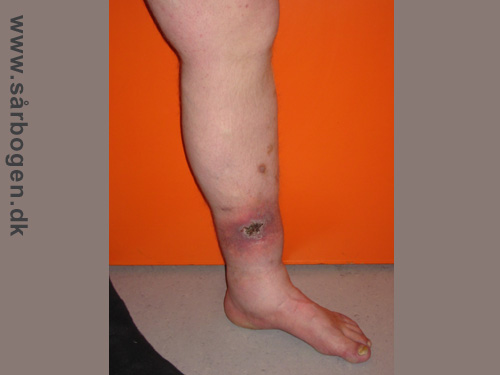

Zoom

Venøst bensår